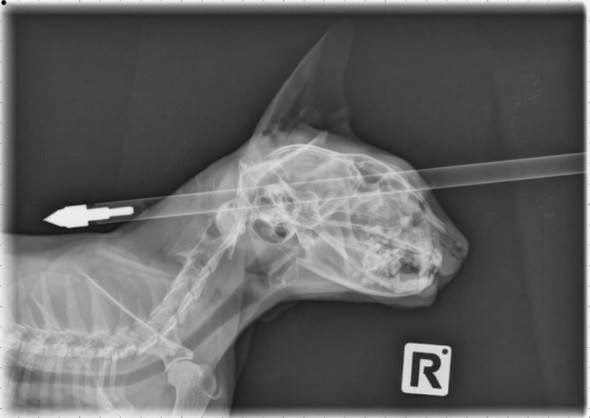

Um gato extraordinariamente sortudo "usou" uma de suas sete vidas depois de sobreviver ao ser alvejado na cabeça por uma flecha.

Espera-se que o afortunado felino "Moo Moo" de quatro anos tenha uma recuperação completa após quase perder o cérebro. Autoridades da Nova Zelândia lançaram uma investigação sobre o incidente, que deixou a proprietária do bichano Donna Ferrari chocada.

A flecha ficou alojada no crânio de Moo Moo acima do olho esquerdo antes de ser removido pela "boquiaberta" equipe de veterinários da Universidade de Massey, em Palmerston North.

"Houve um pouco de dano para o nariz e a órbita ocular, mas ele é um gato de sorte extraordinária", disse o cirurgião veterinário Dr. Jonathan Bray.

"Ele está muito bem - radiante e feliz; a ferida está cicatrizando bem e ele não terá sequelas a longo prazo."